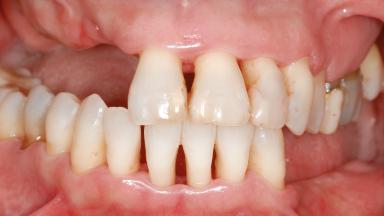

A 46-year-old woman was referred for treatment whose main complaints were mobility of her fixed partial dentures (right maxilla and left mandible) and periodontal bleeding during function. She also reported having taken systemic antibiotics to treat recurrent swelling in the area of the upper left molars. The patient had not seen a dentist for at least 2 years. She did not smoke and had no history of major systemic disease other than two minor orthopedic procedures some years back. The first-visit examination revealed poor plaque control, tooth mobility, periodontal disease, and a residual dentition widely associated with deep periodontal pockets.

Bone Volume Horizontally and vertically sufficient Horizontally deficient Deficient vertically or deficient vertically AND horizontally

Bone Volume Deficient vertically or deficient vertically AND horizontally

Periodontal Status History of periodontitis or genetic predisposition